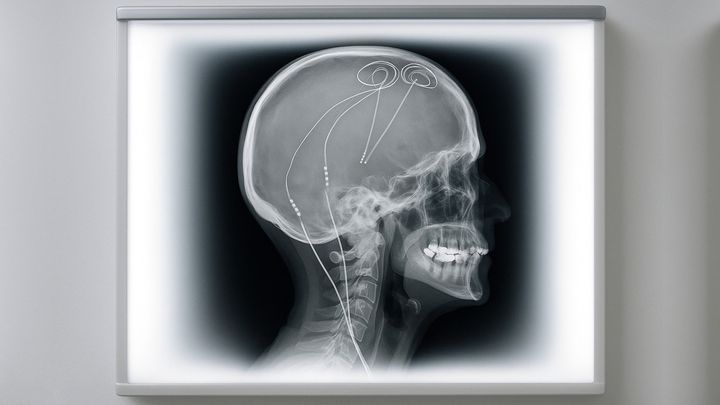

脳電極で「慢性的な痛み」を救う方法が開発された / 脳深部刺激療法(DBS)が行われている患者の脳内の様子を描いたもの/Credit:川勝康弘

DBSは、脳の深い部分に細い電極を入れてごく弱い電気を流すことで、脳の異常な活動をやさしくリセットする治療法です。

「もう治らない」と諦めた慢性痛、脳に埋め込む電極が救った / 脳深部刺激療法(DBS)の参考画像。DBSでは脳の奥深くに電極が差し込まれることがあります/Credit:Tiago Matheus Nordi . Electronics (2022)

次に研究チームは、それぞれの患者さんで見つけた最適なポイントに、小さな電極と装置を入れて、自宅で普段の生活を送りながら、脳の活動(脳波)を記録しました。